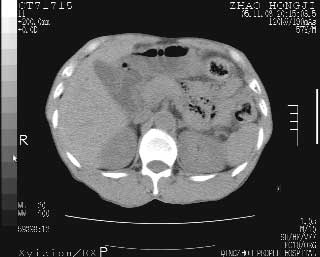

临床资料:男性,57岁,上腹部疼痛并5天,突然加重并延及全腹伴恶心5小时入院。胰淀粉酶化验在正常范围。检查:腹肌紧张,全腹压痛、反跳痛,尤以右上腹部为著。肠鸣音减低。血常规:wbc14.6x10/9, n:11.3x10/9 ,血压:135/90mmhg. 胸部透视:腹部肠腔轻度张气,未见其它异常改变。

肝右前缘少量积气,其他未见明显异常.考虑上消化道穿孔.

小网膜囊积气液,胃壁僵硬。考虑胃穿孔。

小膜网膜积液,肝缘气腹征,上消化道穿孔。

胰腺形态规则,胰周脂肪间隙清晰,结合临床可排除急性胰腺炎

从图提示我同意空腔脏器穿孔的诊断,来源肠道{由于病程较短,故没能见到肠系膜聚局的征象}。

肝缘见少许气体,胰尾部见少许气体包饶(蓝色圈),12指肠上部或球部邻近胆囊周边也可见少许气体影(黄色圈),并忖托出胆囊壁,12指肠远段肠道内未见明显气体(白色箭)。

肝脏前缘见少量积气、胰尾部见少许气体包饶,肾前筋膜未见增厚,临床淀粉酶不高,意见:上消化道穿孔。

消化道穿孔。12指肠球部周和胰周积气考虑12指肠穿孔可能性大。

入院3小时后行剖腹探查术,见腹腔内大量脓性混浊液约1000ml,十二指肠球部溃疡穿孔,溃疡面约2.5x2cm,穿孔直径约0.6cm。胃内容物外益,周围组织炎性水肿明显。行十二指肠穿孔修补术。术后诊断:

1、十二指肠溃疡穿孔

2、弥漫性腹膜炎

对于少量的腹腔游离气体,ct检查较普通透视有绝对的优势,它不仅可以看到肝脏前上缘的气体,而且还能够看到小网膜区的游离气体。从而可以肯定诊断。各位分析战友的很好,感谢大家的参入!